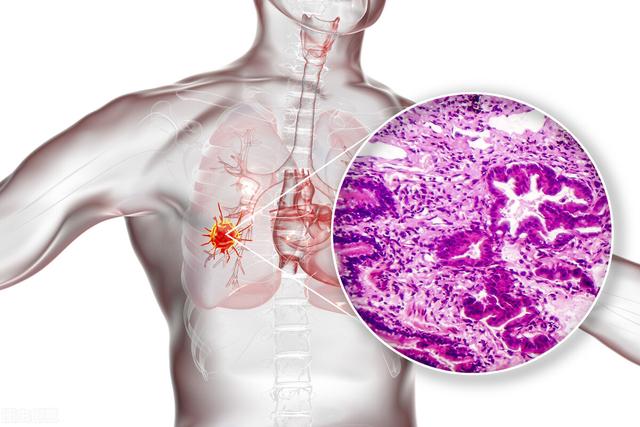

Les cancers du poumon sont classés en adénocarcinome, carcinome malpighien, carcinome à grandes cellules, carcinome à petites cellules, carcinome carcinoïde, etc. Lorsque ces cancers sont de petite taille, ils ne sont pas aussi typiques que lorsqu'ils sont de grande taille.

Il s'agit d'un cas d'adénocarcinome pulmonaire confirmé chirurgicalement.

Les lésions d'hyperplasie adénomateuse atypique sont généralement inférieures à 5 mm et dépassent relativement rarement 8 mm. Ci-dessous, le scanner et la pathologie d'une hyperplasie adénomateuse atypique de 8 mm.

Pour les nodules en verre dépoli qui ne sont pas considérés comme ayant atteint le stade de l'opportunité chirurgicale, ou qui peuvent être au stade d'hyperplasie adénomateuse atypique.Quelles sont les affections qui nécessitent une intervention chirurgicale immédiate ?? Le lecteur du film doit comparer attentivement les lésions avant et après, et si elles s'avèrent êtreLa lésion est légèrement plus grande que la précédente, voire légèrement plus dense, ou un vaisseau sanguin s'est développé dans la lésion.C'est l'heure de la chirurgie, par exemple, dans l'image ci-dessous.